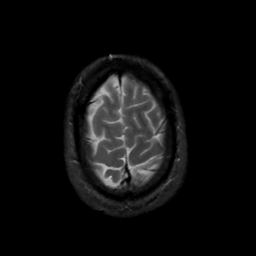

MR Study #13, May 19, 1991 -- Slice #44

[Home][Help][Clinical][Tour 1][Tour 2] Slice 44